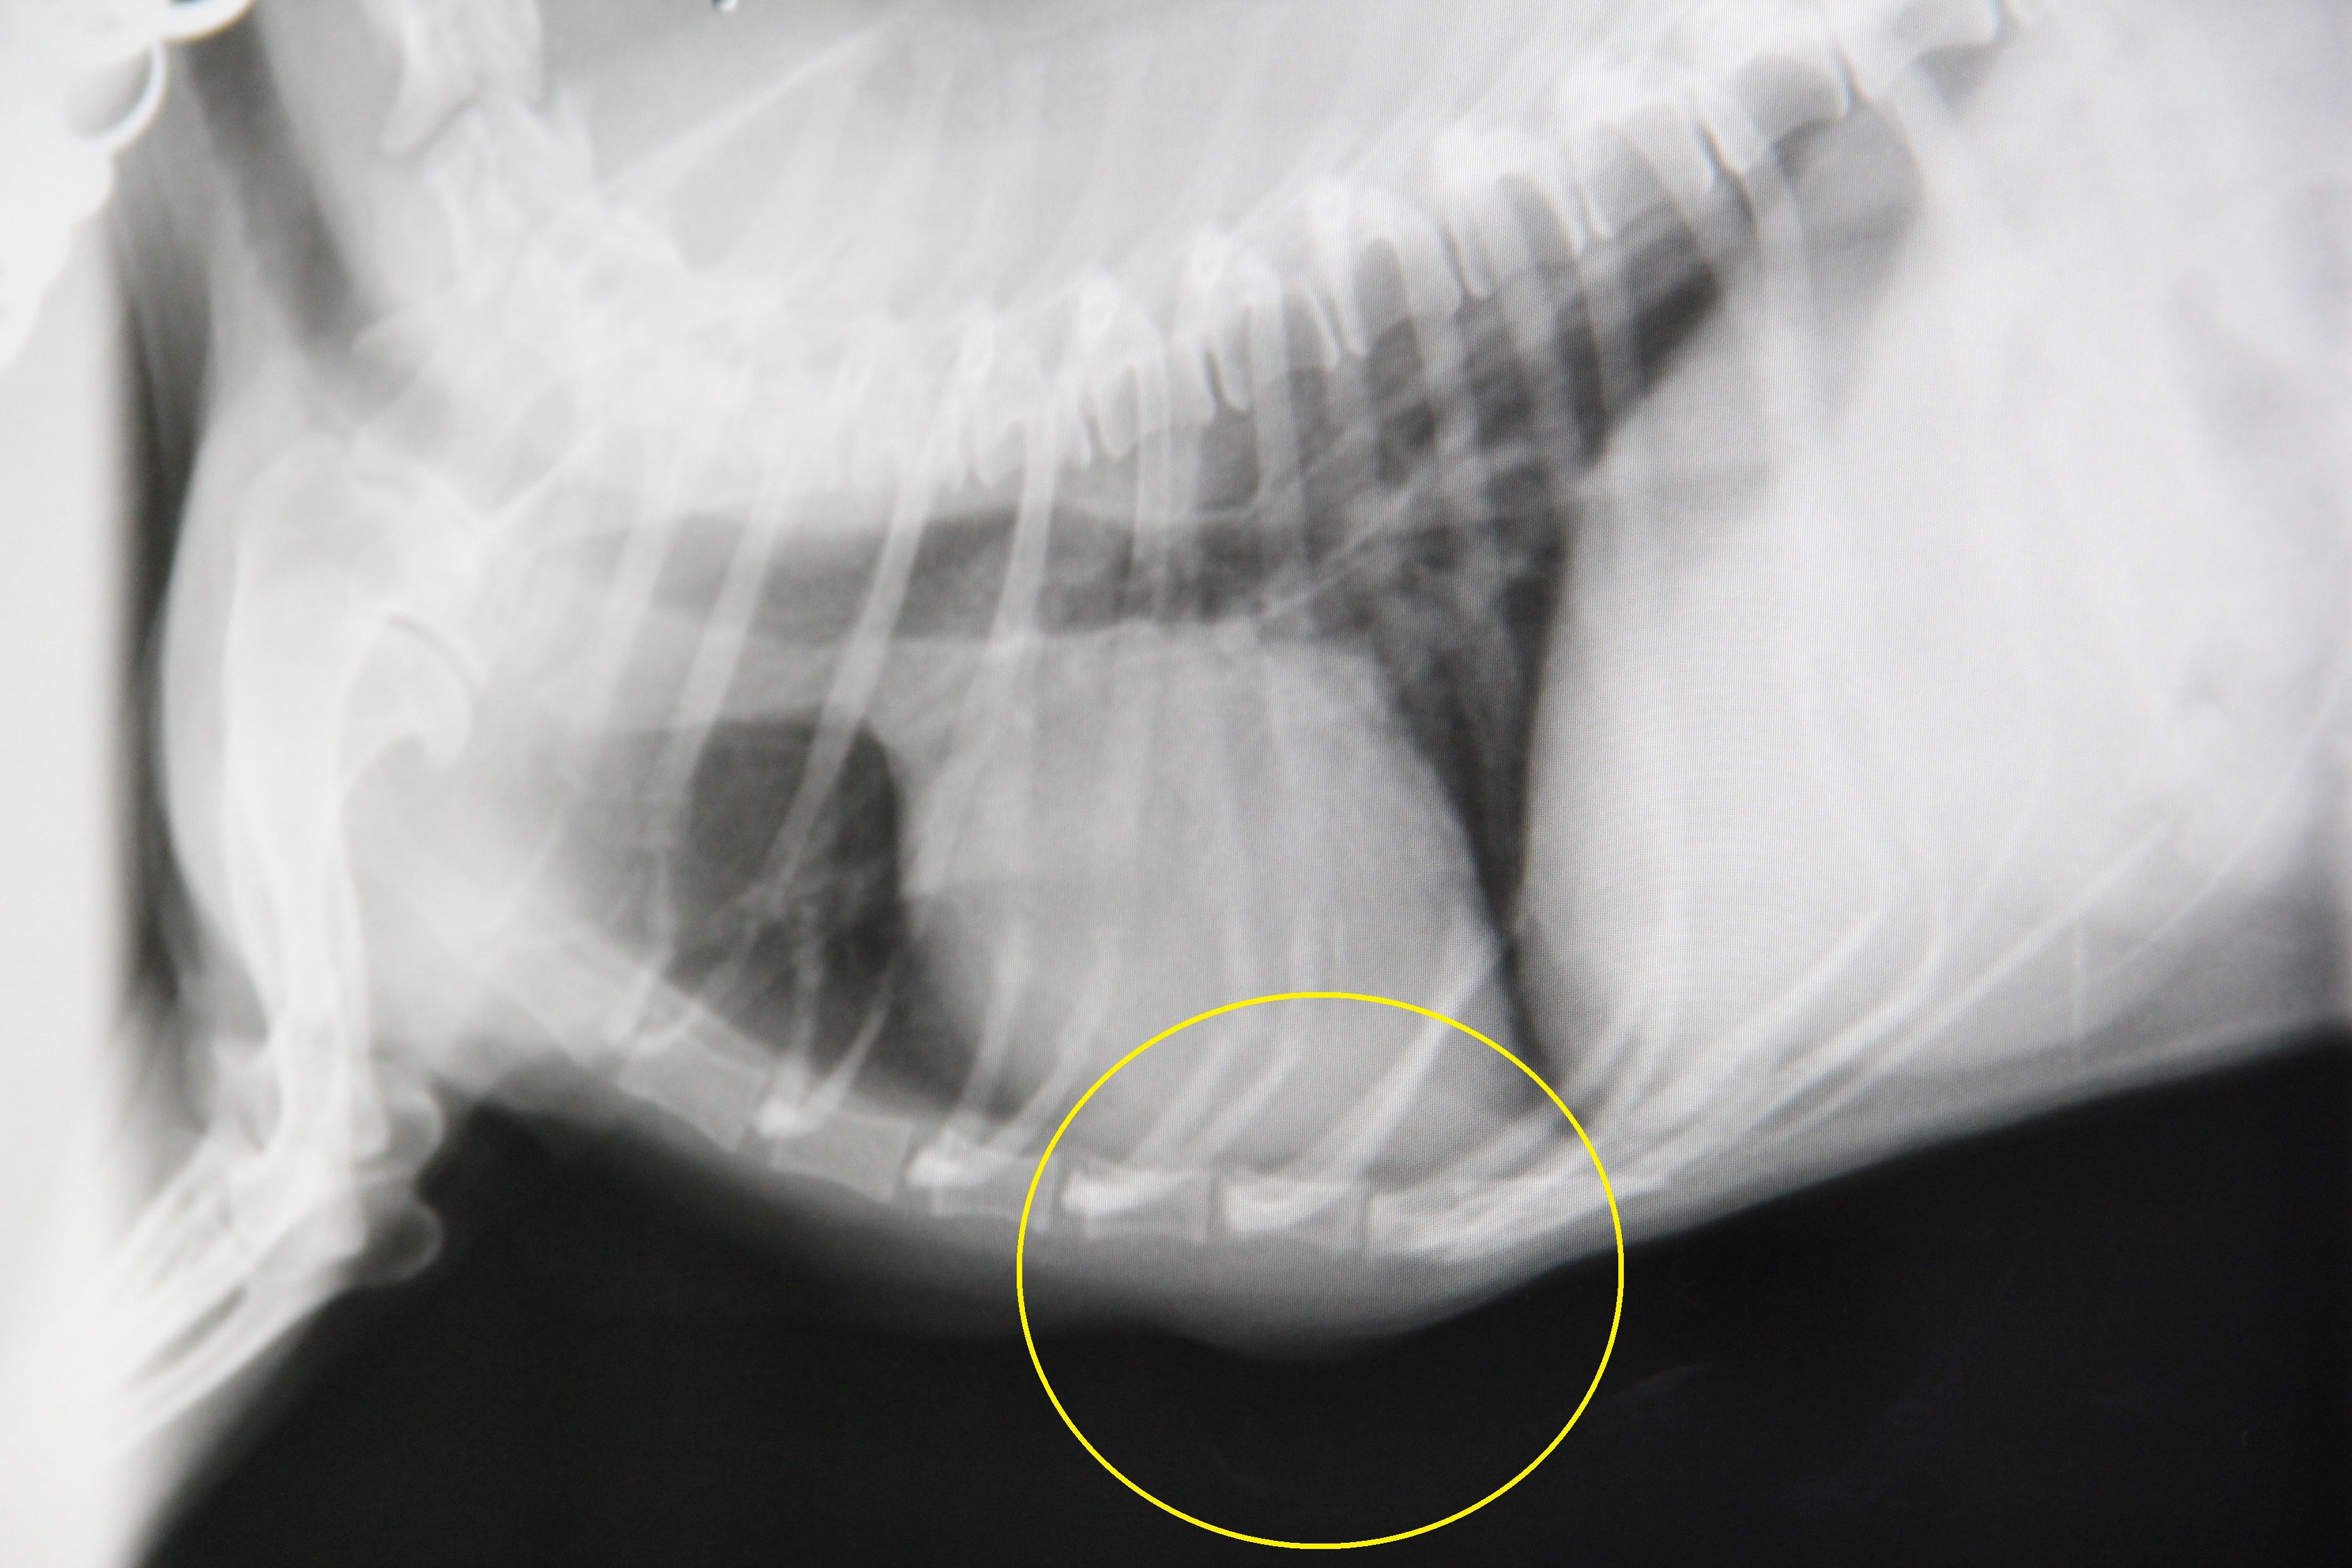

気になることがあって病院で診察だ ▼・。・▼… 2025年10月19日